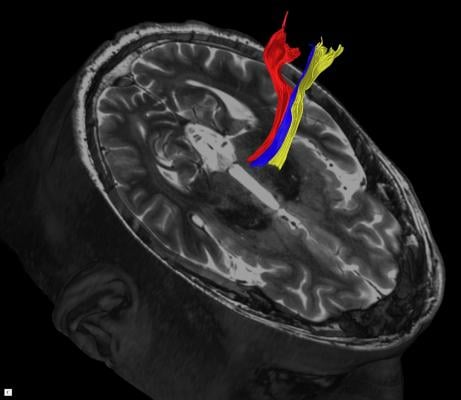

Diffusion tractography uses the movement of water molecules to identify tracts that connect different parts of the brain. It can be used to pinpoint the part of the thalamus to treat with focused ultrasound. Image courtesy of UT Southwestern Medical Center

The most widely studied and perhaps most promising imaging method is called diffusion tractography, said Shah. It creates precise brain images by taking into account the natural water movement within tissues.